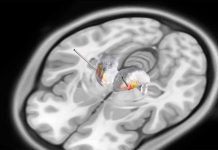

Pensando fuera de la caja: Descubriendo un nuevo enfoque para el monitoreo de ondas...

ROCHESTER, Minnesota — Investigadores de Mayo Clinic han descubierto una nueva manera de detectar y monitorear con mayor precisión la actividad de las células...